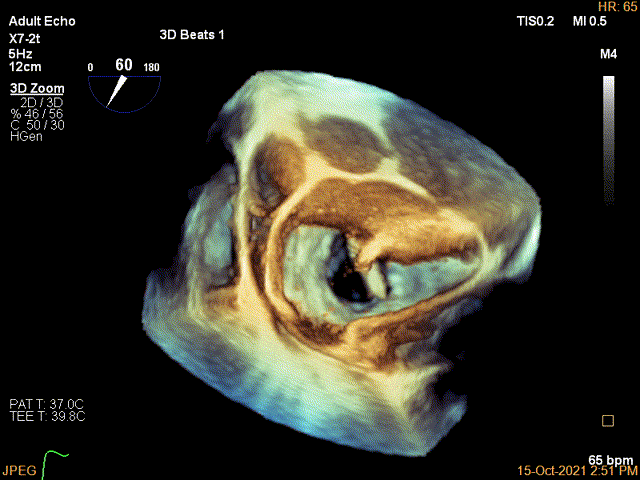

3D-color MV view:极大量返流,1、2区均有受累

3D视图下开夹子并调Rotate

3D证实夹子内侧残余Flail

3D-color证实残余分流主要位于内侧2区

3D视图两个夹子近似并排排列,排列很紧密